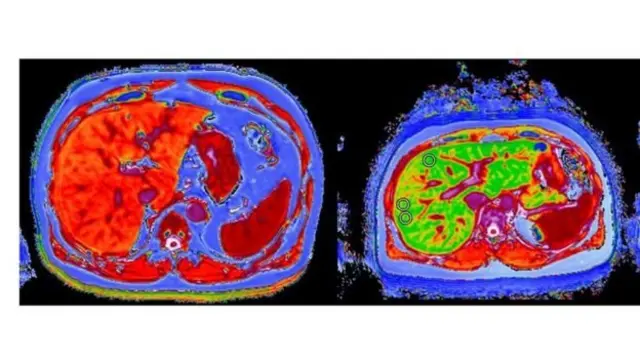

،تصویر کا ذریعہPERSPECTUM DIAGNOSTICS

انھوں نے اب نئی قسم کا ایم آر آئی سکین کرایا ہے جس میں پتہ چلا ہے کہ اب ان کا جگر پھر سے تندرست و توانا ہے۔

یہ ٹیسٹ ایک جدید سافت ویئر کی مدد سے مکمل ہو سکا ہے۔ اسے آکسفورڈ یونیورسٹی کی پرسپیکٹم ڈائگناسٹک کمپنی نے تیار کیا ہے۔

انھوں نے کہا کہ 'سکین سے سارے جگر کا نقشہ سامنے آ جاتا ہے جبکہ سوئی سے صرف ایک حصے کا نمونہ ملتا ہے اور یہ ناخوشگوار بھی ہوتا ہے۔

'اس میں یہ آسانی بھی ہے کہ ہم مریض کا پھر سے سکین کر سکتے ہیں اور یہ جان سکتے ہیں کہ آیا کوئی فائدہ ہوا ہے۔'